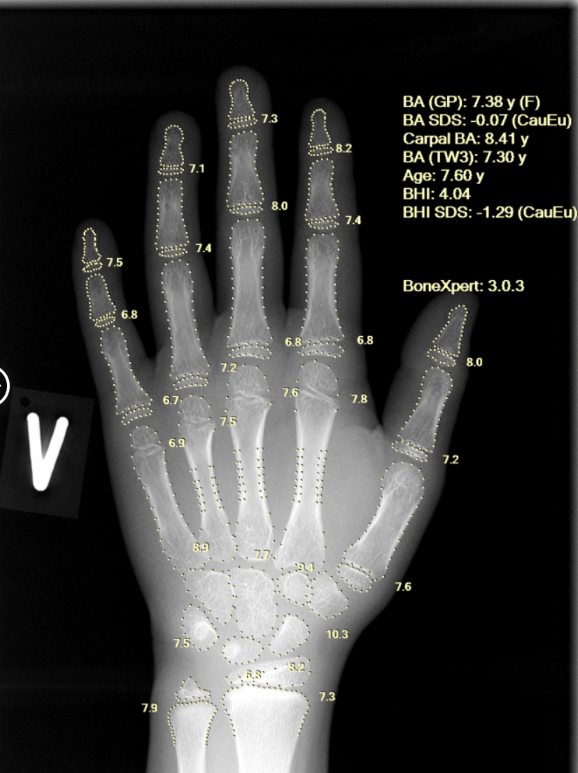

Kapadia Hospital Introduces MISSO, AI-Powered Orthopaedic Surgery System

This new system uses specialised software that can take into account real-time data to build an accurate 3D model of each individual patient’s anatomy...